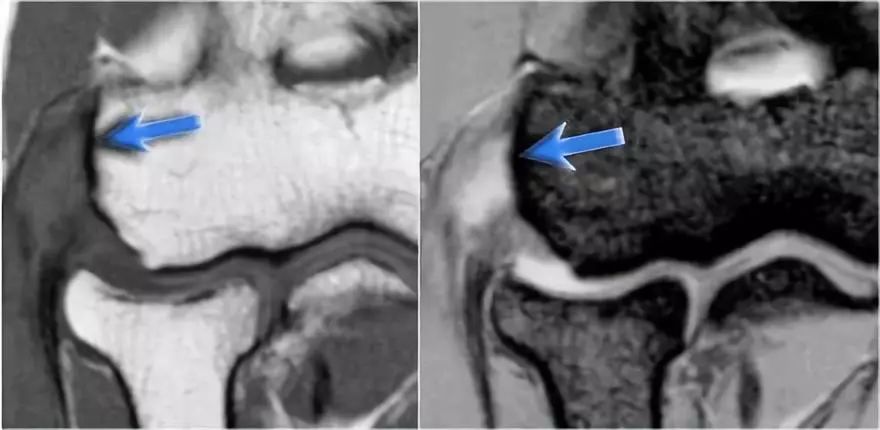

冠状图像上有一个美丽的UCL前束,但注意到关节内侧部分有骨赘形成(红色箭头)。当我们按照顺序向下看,可以看到存在一小部分低信号强度(黄色箭头),这是UCL的一部分撕裂。

这是在X线片可以更好地观察(黄箭头 )。

当我们看轴向扫描时,我们可以欣赏巨大的骨赘形成。请注意,尺骨神经(蓝色箭头)紧邻这些骨赘,这些可能指示尺神经出现病变。